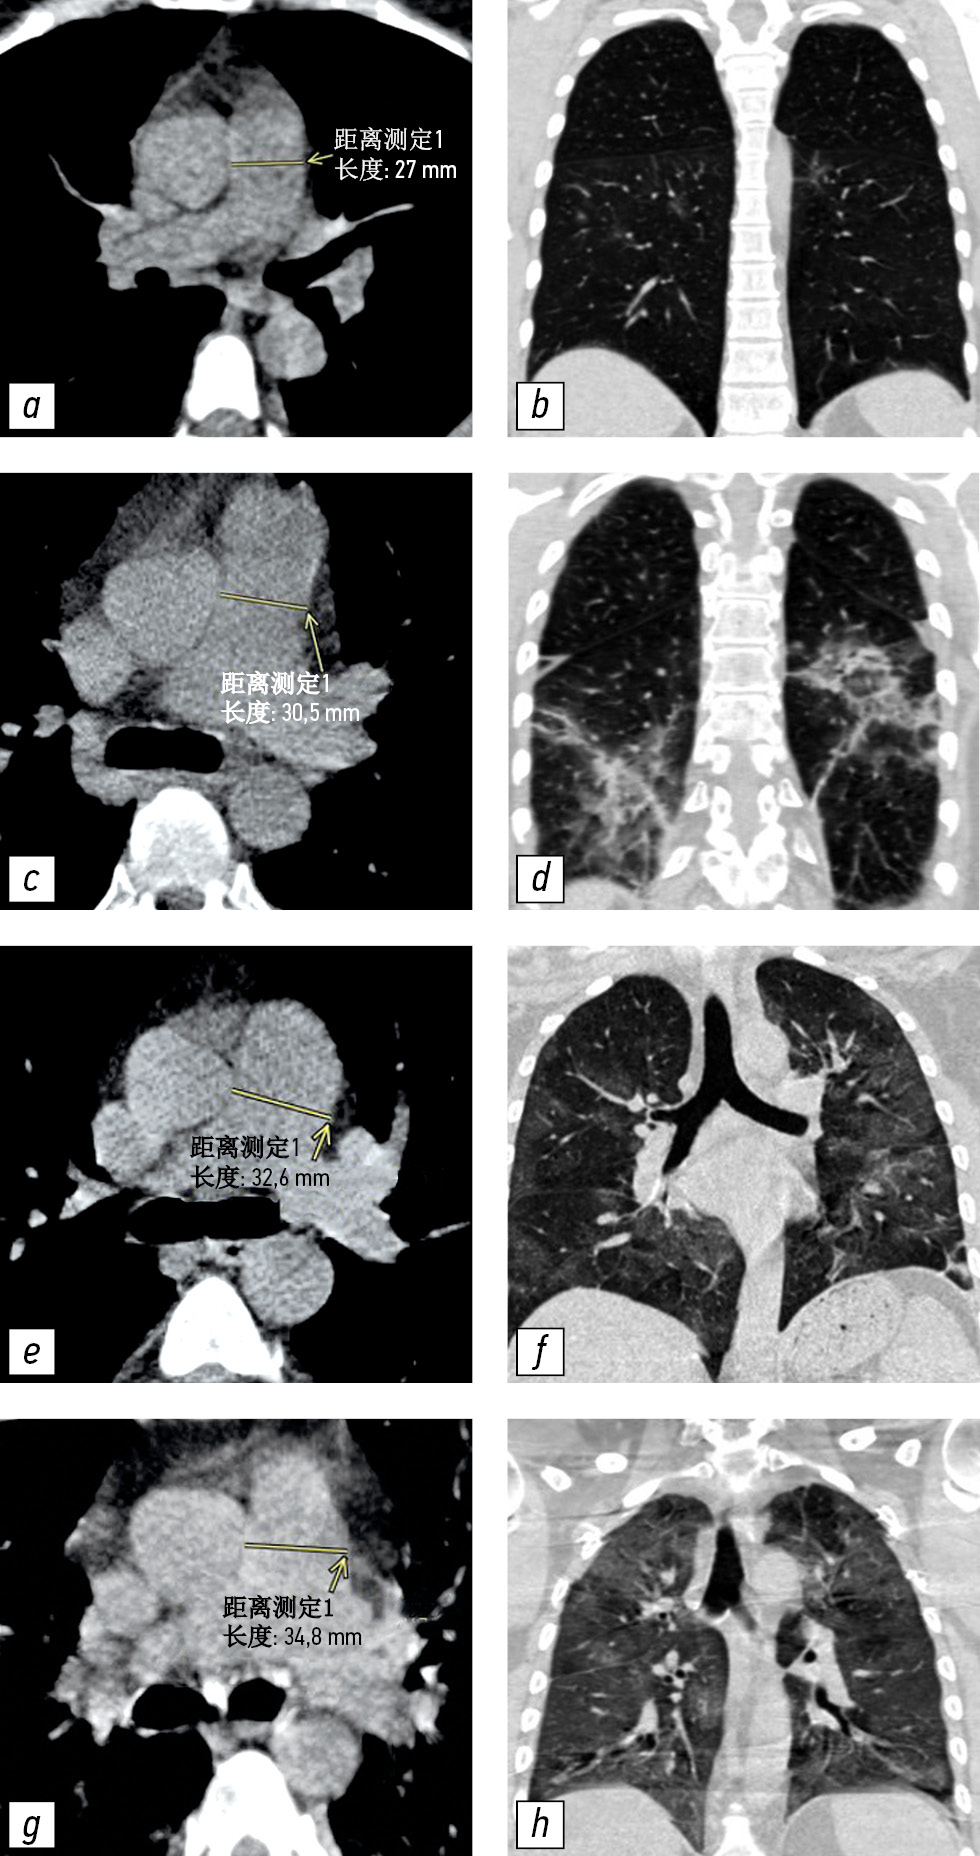

不同体积肺实质病变患者的CT图像及相应的肺动脉测量值在图3提出。

图 3 具有不同 PA 直径和肺部受累程度的 CT 图像示例:a、b - 未扩张的 PA(27.0 毫米),CT-1 肺部受累程度(小于 25%); c, d - 肺损伤程度 CT-2 (25-50%) 增大的 PA (30.5 毫米); e, f - 扩张的 PA (32.6毫米),肺损伤程度为 KT-3 (50–75%); g, h - 肺损伤程度 CT-4(大于 75%)的扩张 PA(34.8毫米)。 CT - 计算机断层扫描; CT 1-4 - 用于视觉评估患者全身状况严重程度对 COVID-19 肺部变化的放射学迹象的性质和严重程度的依赖性的改编量表; PA-肺动脉。